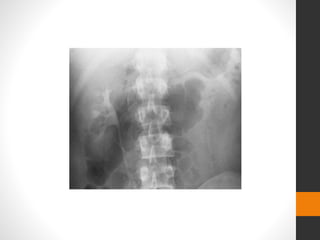

KUB

โ€ข Plain abdominal radiography

โ€ข assessing total stone burden, as well as the size, shape

โ€ข location of urinary calculi

โ€ข Calcium-containing are radiopaque

โ€ข the progress of the stone can be easily monitored with a

follow-up KUB

Many calcifications on the KUB radiograph are:

โ€ข phleboliths, vascular calcifications, calcified lymph

nodes, appendicoliths, granulomas or even bowel

Plain film showing large right staghorn calculus.